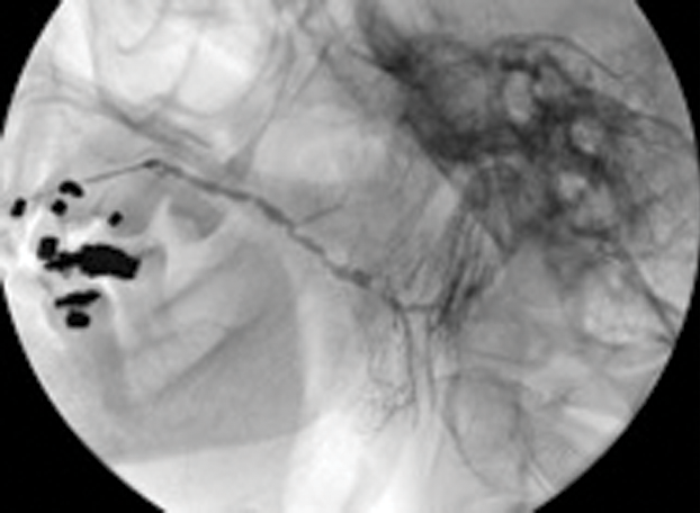

Figure 4: (A) Sialogram showing multiple stenoses located in the parotid duct before treatment.

Figure 4: (B) Appearance on sialogram following balloon dilatation.

Treatment of salivary duct stenosis by interventional sialography

Salivary duct stenosis is a surprisingly frequent phenomenon, being the prime cause in 24% of all cases of benign salivary gland obstruction in a study by Ngu. Strictures of 75% were found in the parotid ducts, and women were affected in 72% of cases [2]. This represents a substantial body of symptomatic individuals who may seek symptomic relief but who frequently do not feel that a surgical solution, such as superficial parotidectomy, with its attendant risks and complications, is justified.

Ductoplasty involves insertion of a fine angioplasty balloon using an on-the-wire-technique into the salivary duct, and manipulation of the balloon catheter through the duct stenosis. Again this is performed under radiological guidance and local anaesthesia. The balloon is inflated, the dilatation being maintained or repeated to eliminate any waisting in the balloon.

Our study has shown a 92% success rate in achieving balloon dilatation, with 82% demonstrating complete elimination of the stricture postoperatively [13].